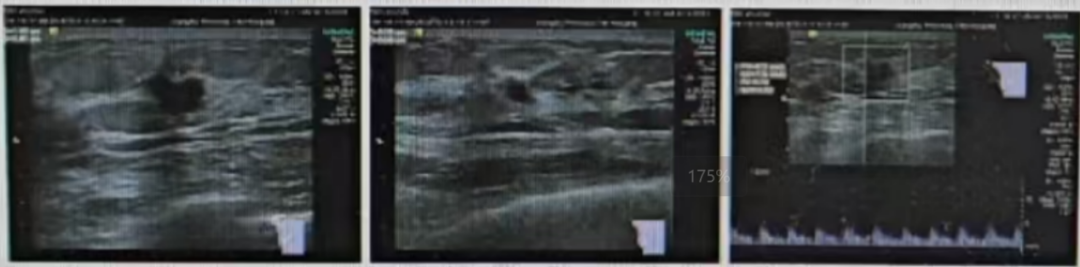

·乳腺彩超

1、右乳9点见一个低回声区,大小约0.53*0.63cm,呈直立生长,边缘成角、毛刺,内部回声不均匀,肿块内未见强回声,BIRADS 5类;

2、右乳10点见一个低回声区,大小约1.4*0.9cm,边缘成角、毛刺,内部回声不均匀,肿块内未见强回声,BIRADS 5类。

图1乳腺彩超结果